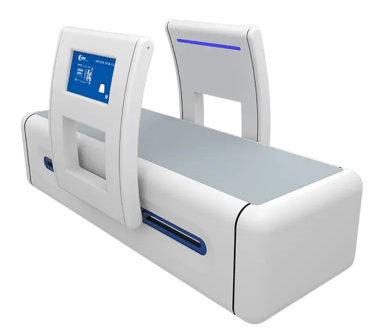

MBST Therapy Advanced Non-Surgical Solution for Joint & Spine Pain

MBST is an innovative German technology that uses therapeutic magnetic resonance to stimulate cell regeneration, repair cartilage, and relieve chronic pain without surgery, injections, or radiation.

Advanced medical technology focused on cellular repair

When pain, stiffness, or injury disrupt your life, real relief should target the source not just cover up the symptoms. MBST offers a different path. By acting directly on the cells where damage begins, it aims to ease pain, reduce inflammation, and improve mobility for people dealing with musculoskeletal issues, chronic discomfort, or long-term conditions.

This approach can help you recover sooner after an injury, move with greater comfort, and maintain the activities you enjoy with more confidence. And with research indicating benefits that continue long after the treatment series ends, MBST supports people of all ages in staying active and mobile for longer.

MBST uses precise magnetic resonance signals to create conditions that support healthy cell activity and natural repair. When cells operate the way they’re meant to, they can better restore balance, regenerate tissue, relieve discomfort, and reduce inflammation.

Chronic inflammation can interrupt these processes and slow down healing. By helping to bring this inflammation under control, MBST promotes more efficient cellular function, allowing your body’s own repair mechanisms to work stronger and deliver long-lasting recovery.